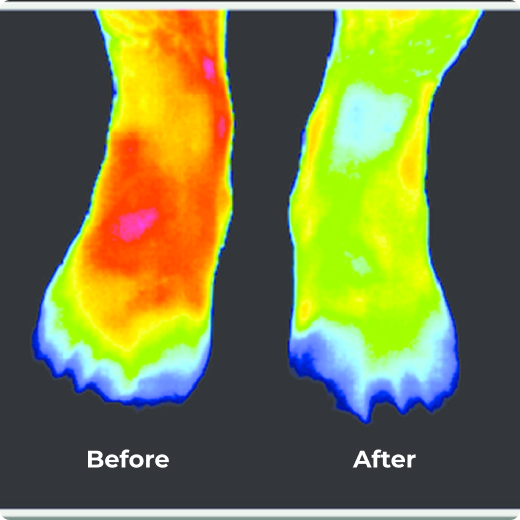

Struggling With Neuropathic Foot Pain, Burning, Stabbing, or Numbness? Get Relief In Just 15 Minutes A Day!

Feel Relief in Just 10 Minutes a Day with Advanced Red Light Technology!